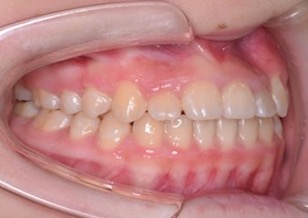

矯正後

After Ⅳ

治療結果として、非抜歯にて上下顎歯列ともに整ったキレイな歯並びとなり、前歯部の反対咬合(受け口)は改善され正常で機能的な咬み合わせが得られました。

After Ⅳのお写真は、埋伏していた上顎左側犬歯を牽引途中のお写真です。